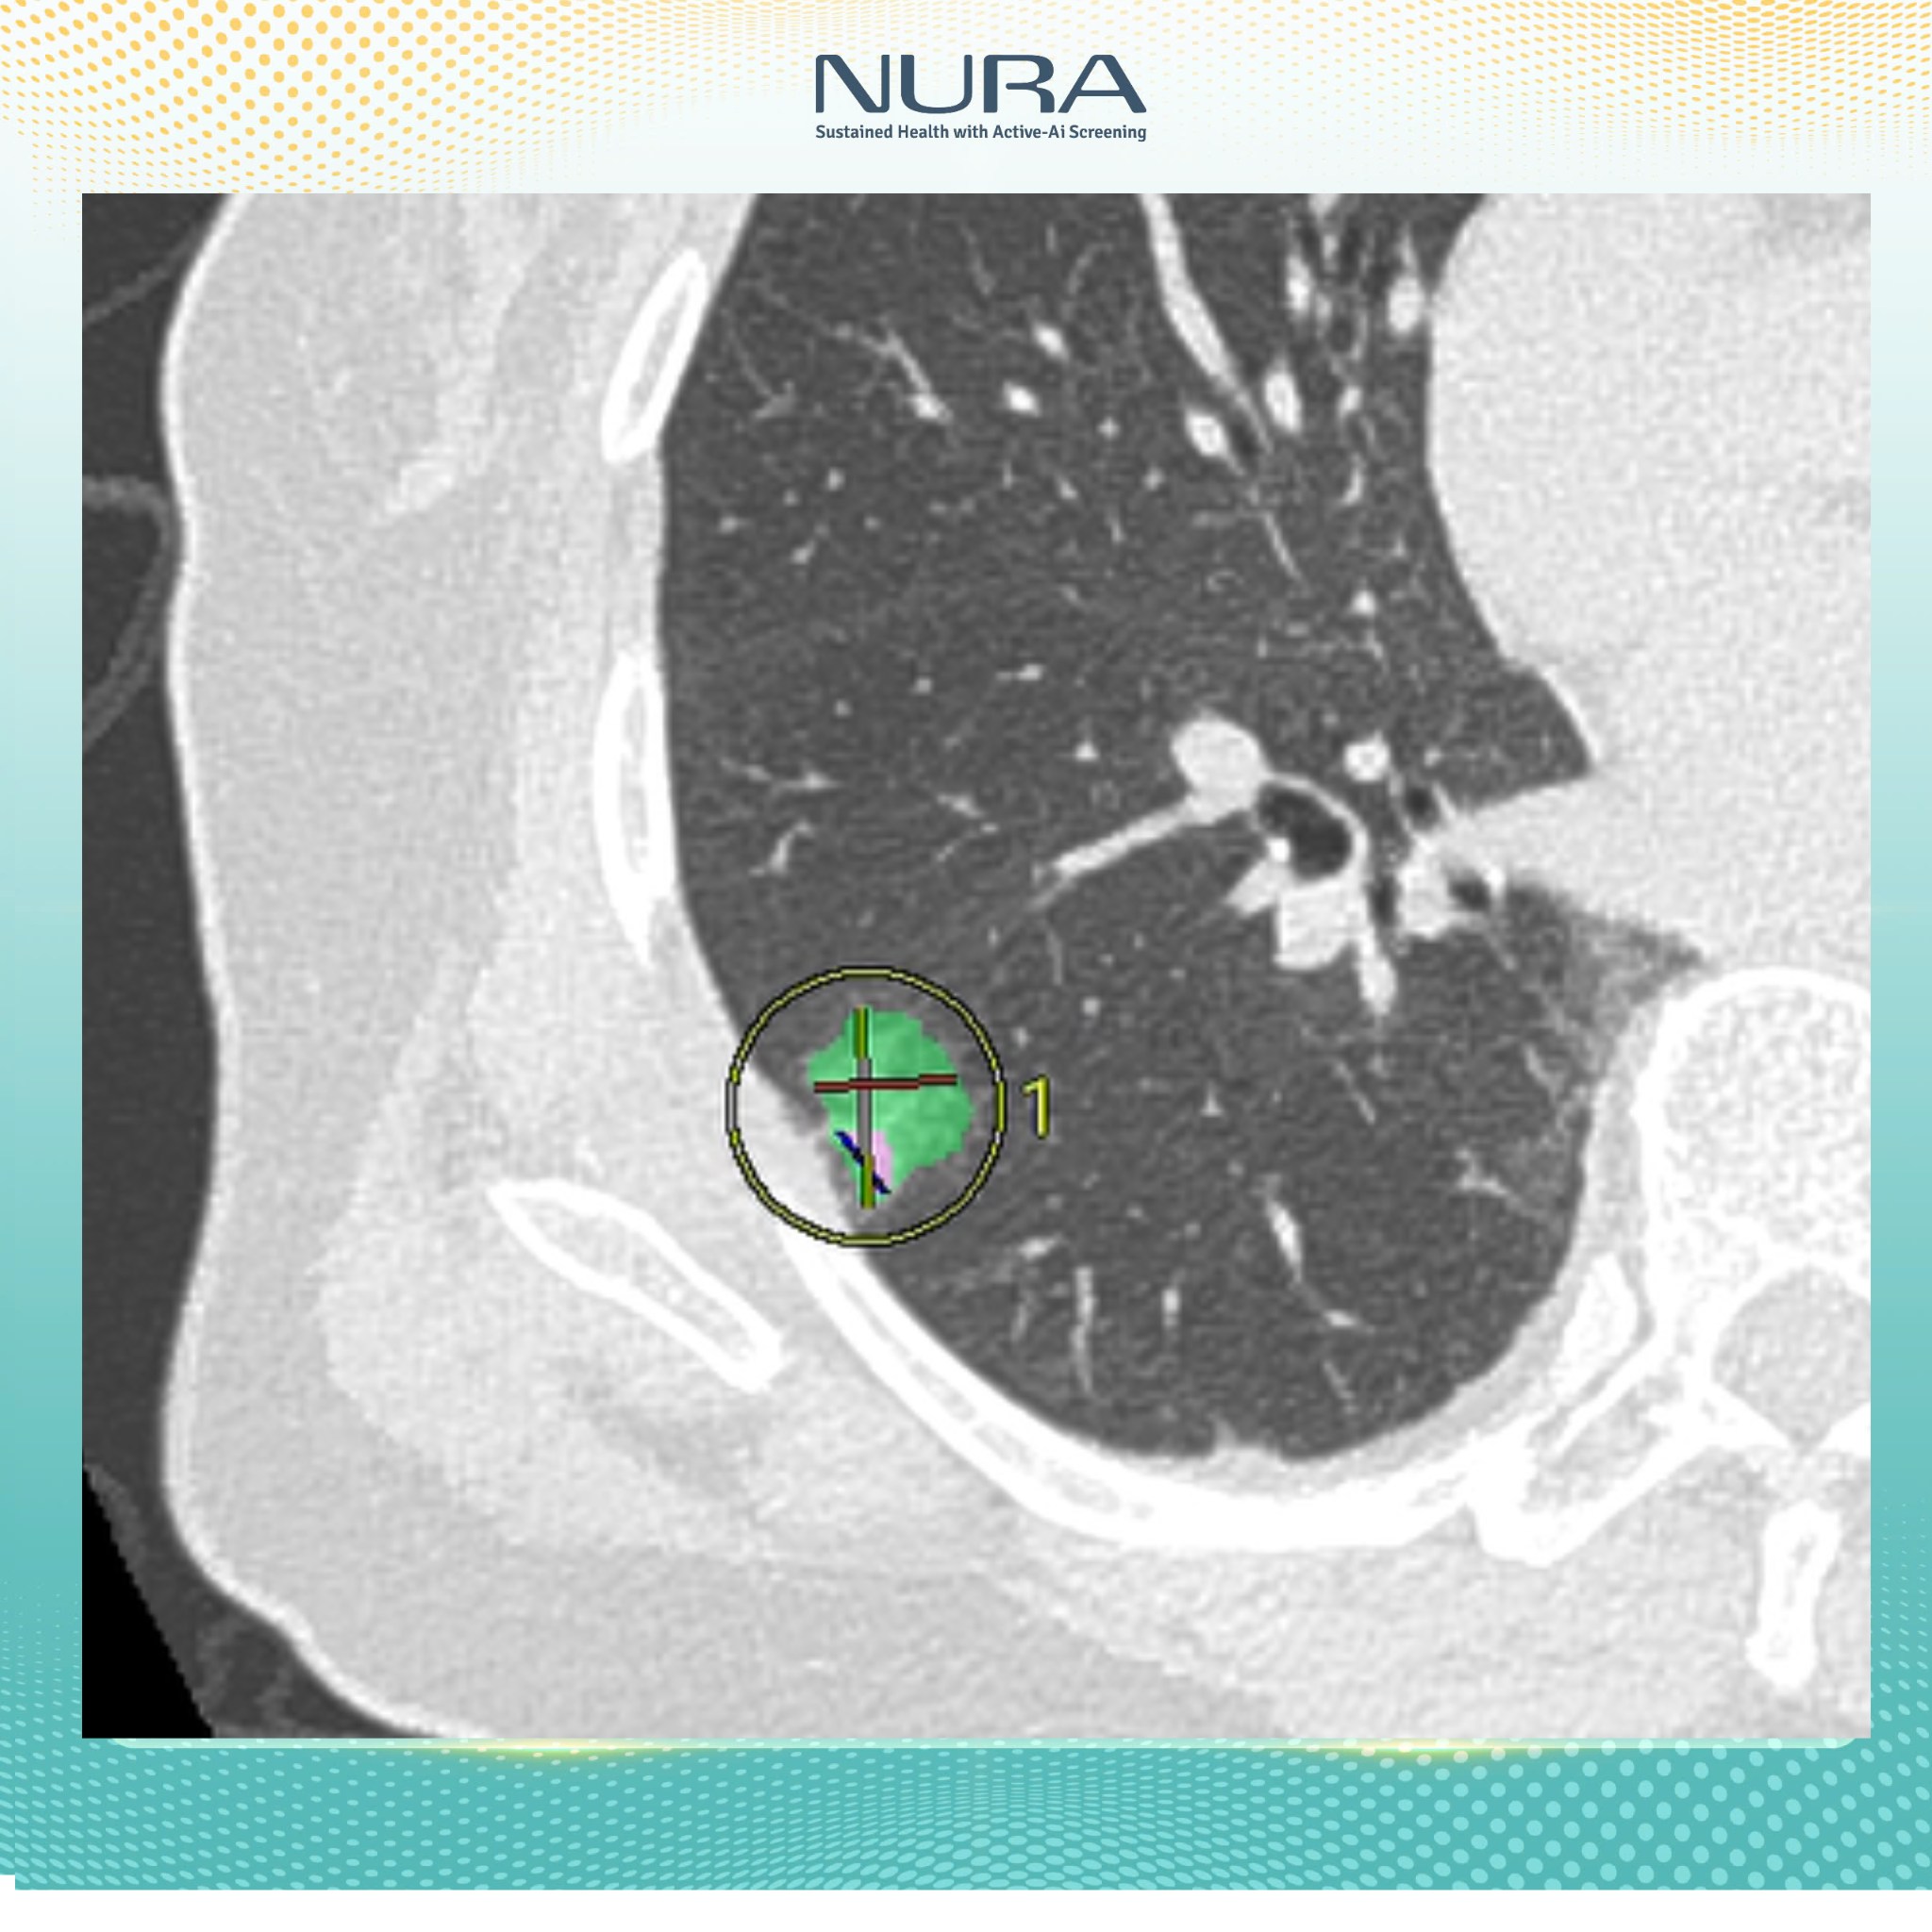

Trong số các thiết bị nổi bật tại trung tâm, máy chụp CT tại đây đã được các bác sĩ Nhật Bản công nhận là “chìa khóa vàng” trong tầm soát phát hiện ung thư. Được vận hành bởi đội ngũ bác sĩ giàu kinh nghiệm và tích hợp AI, hệ thống máy chụp này không chỉ giúp phát hiện các tổn thương rất nhỏ mà còn đảm bảo an toàn tối đa cho người được thăm khám.

“Công nghệ AI của NURA không chỉ đơn thuần là công cụ hỗ trợ, mà còn đóng vai trò quan trọng trong quy trình phân tích và nhận diện hình ảnh. Bằng cách thu thập và xử lý dữ liệu hình ảnh y khoa từ hơn 400 triệu ca bệnh được Fujifilm Nhật Bản lưu trữ trong suốt 10 năm, AI có thể nhận diện sớm các tổn thương bất thường – từ những nốt nhỏ nhất, kích thước từ 1mm trở lên.

Tại NURA, công nghệ AI được tích hợp trong hệ thống tầm soát công nghệ cao, cho phép lưu trữ và phân tích dữ liệu hình ảnh rõ nét, vượt trội so với phương pháp chụp cắt lớp truyền thống”, Đại diện NURA chia sẻ với báo chí.

Chỉ sau vài phút, kết quả sẽ được gửi về dưới dạng các hình ảnh cắt lớp chi tiết. Những lát cắt này cho phép bác sĩ phát hiện các tổn thương có kích thước từ 1mm, giúp việc chẩn đoán trở nên chính xác và nhanh chóng hơn rất nhiều.

- Về tính chính xác: AI không chỉ giúp phát hiện tổn thương từ rất sớm, mà còn tự động đo kích thước từng nốt nghi ngờ, đếm số lượng, đánh giá mức độ nguy cơ và hỗ trợ bác sĩ trong việc đưa ra quyết định chuyên sâu.